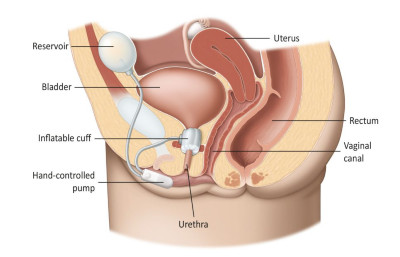

Είναι το συχνότερο είδος ακράτειας στις γυναίκες και οφείλεται στην χαλάρωση του πυελικού εδάφους (Εικ.1) αλλά και στην εμμηνόπαυση.

Εικ.1: Το γυναικείο Πυελικό Έδαφος